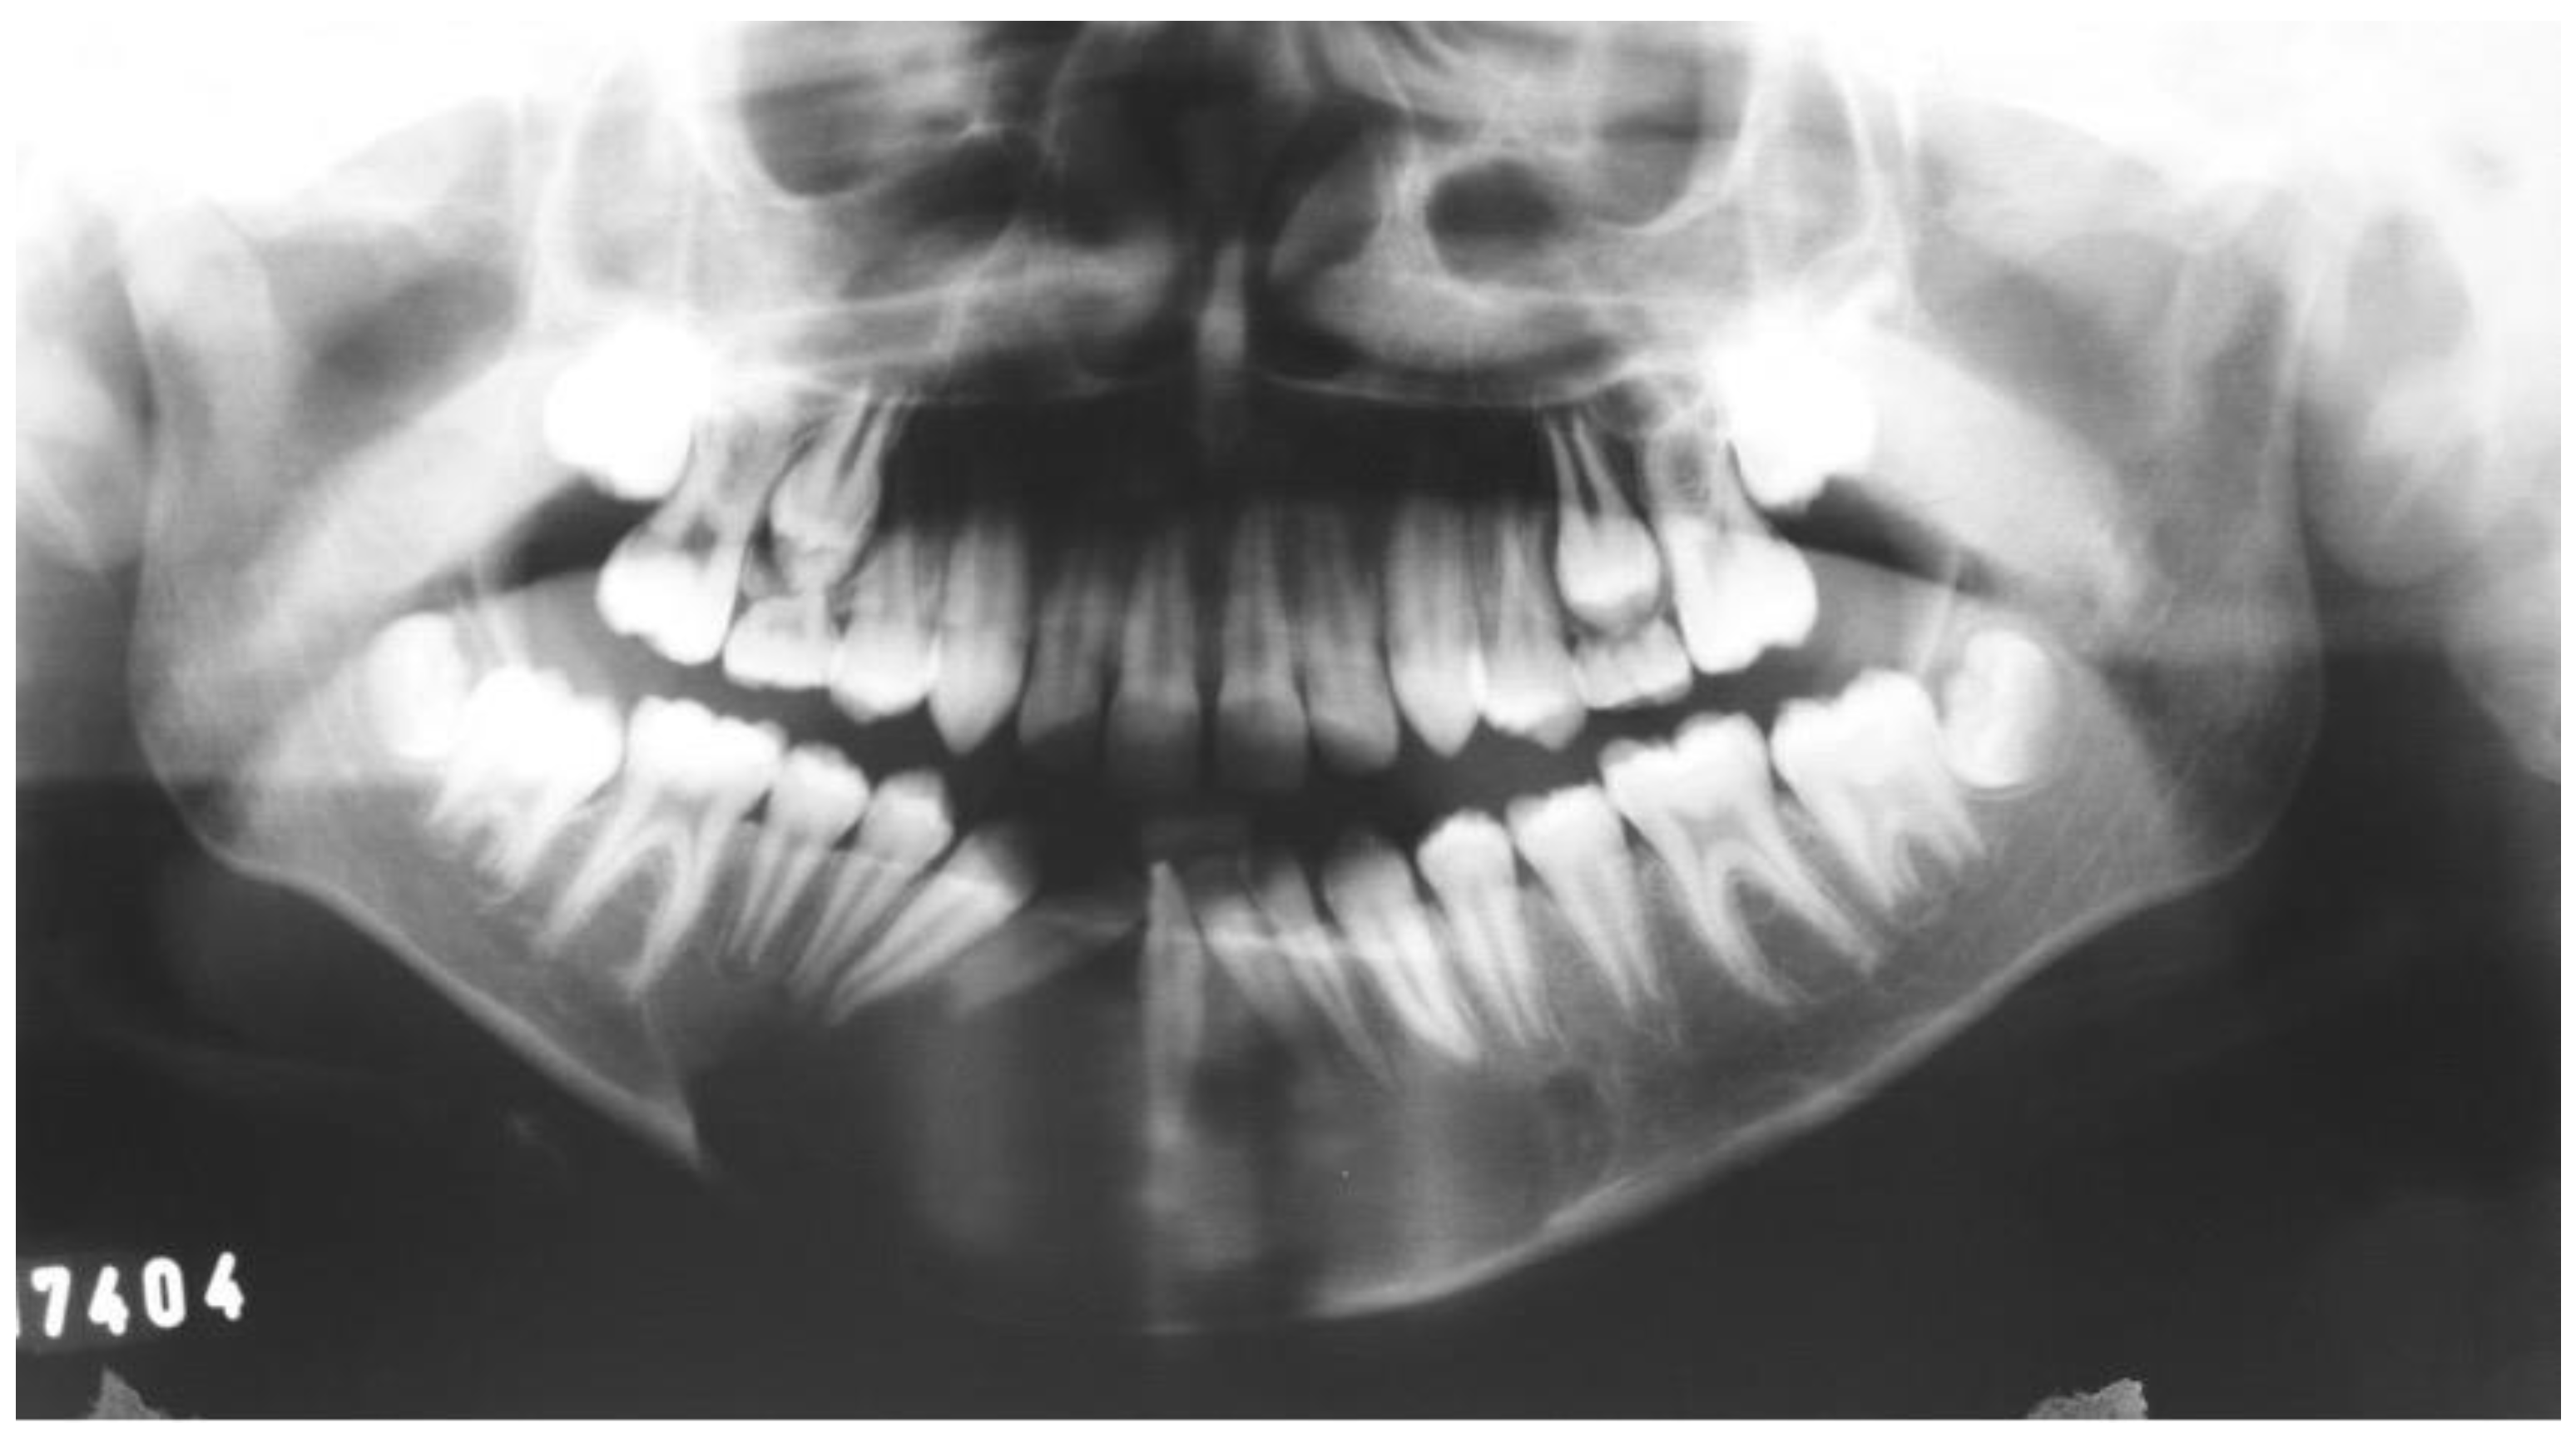

2.1. Case 1

2.2. Case 2